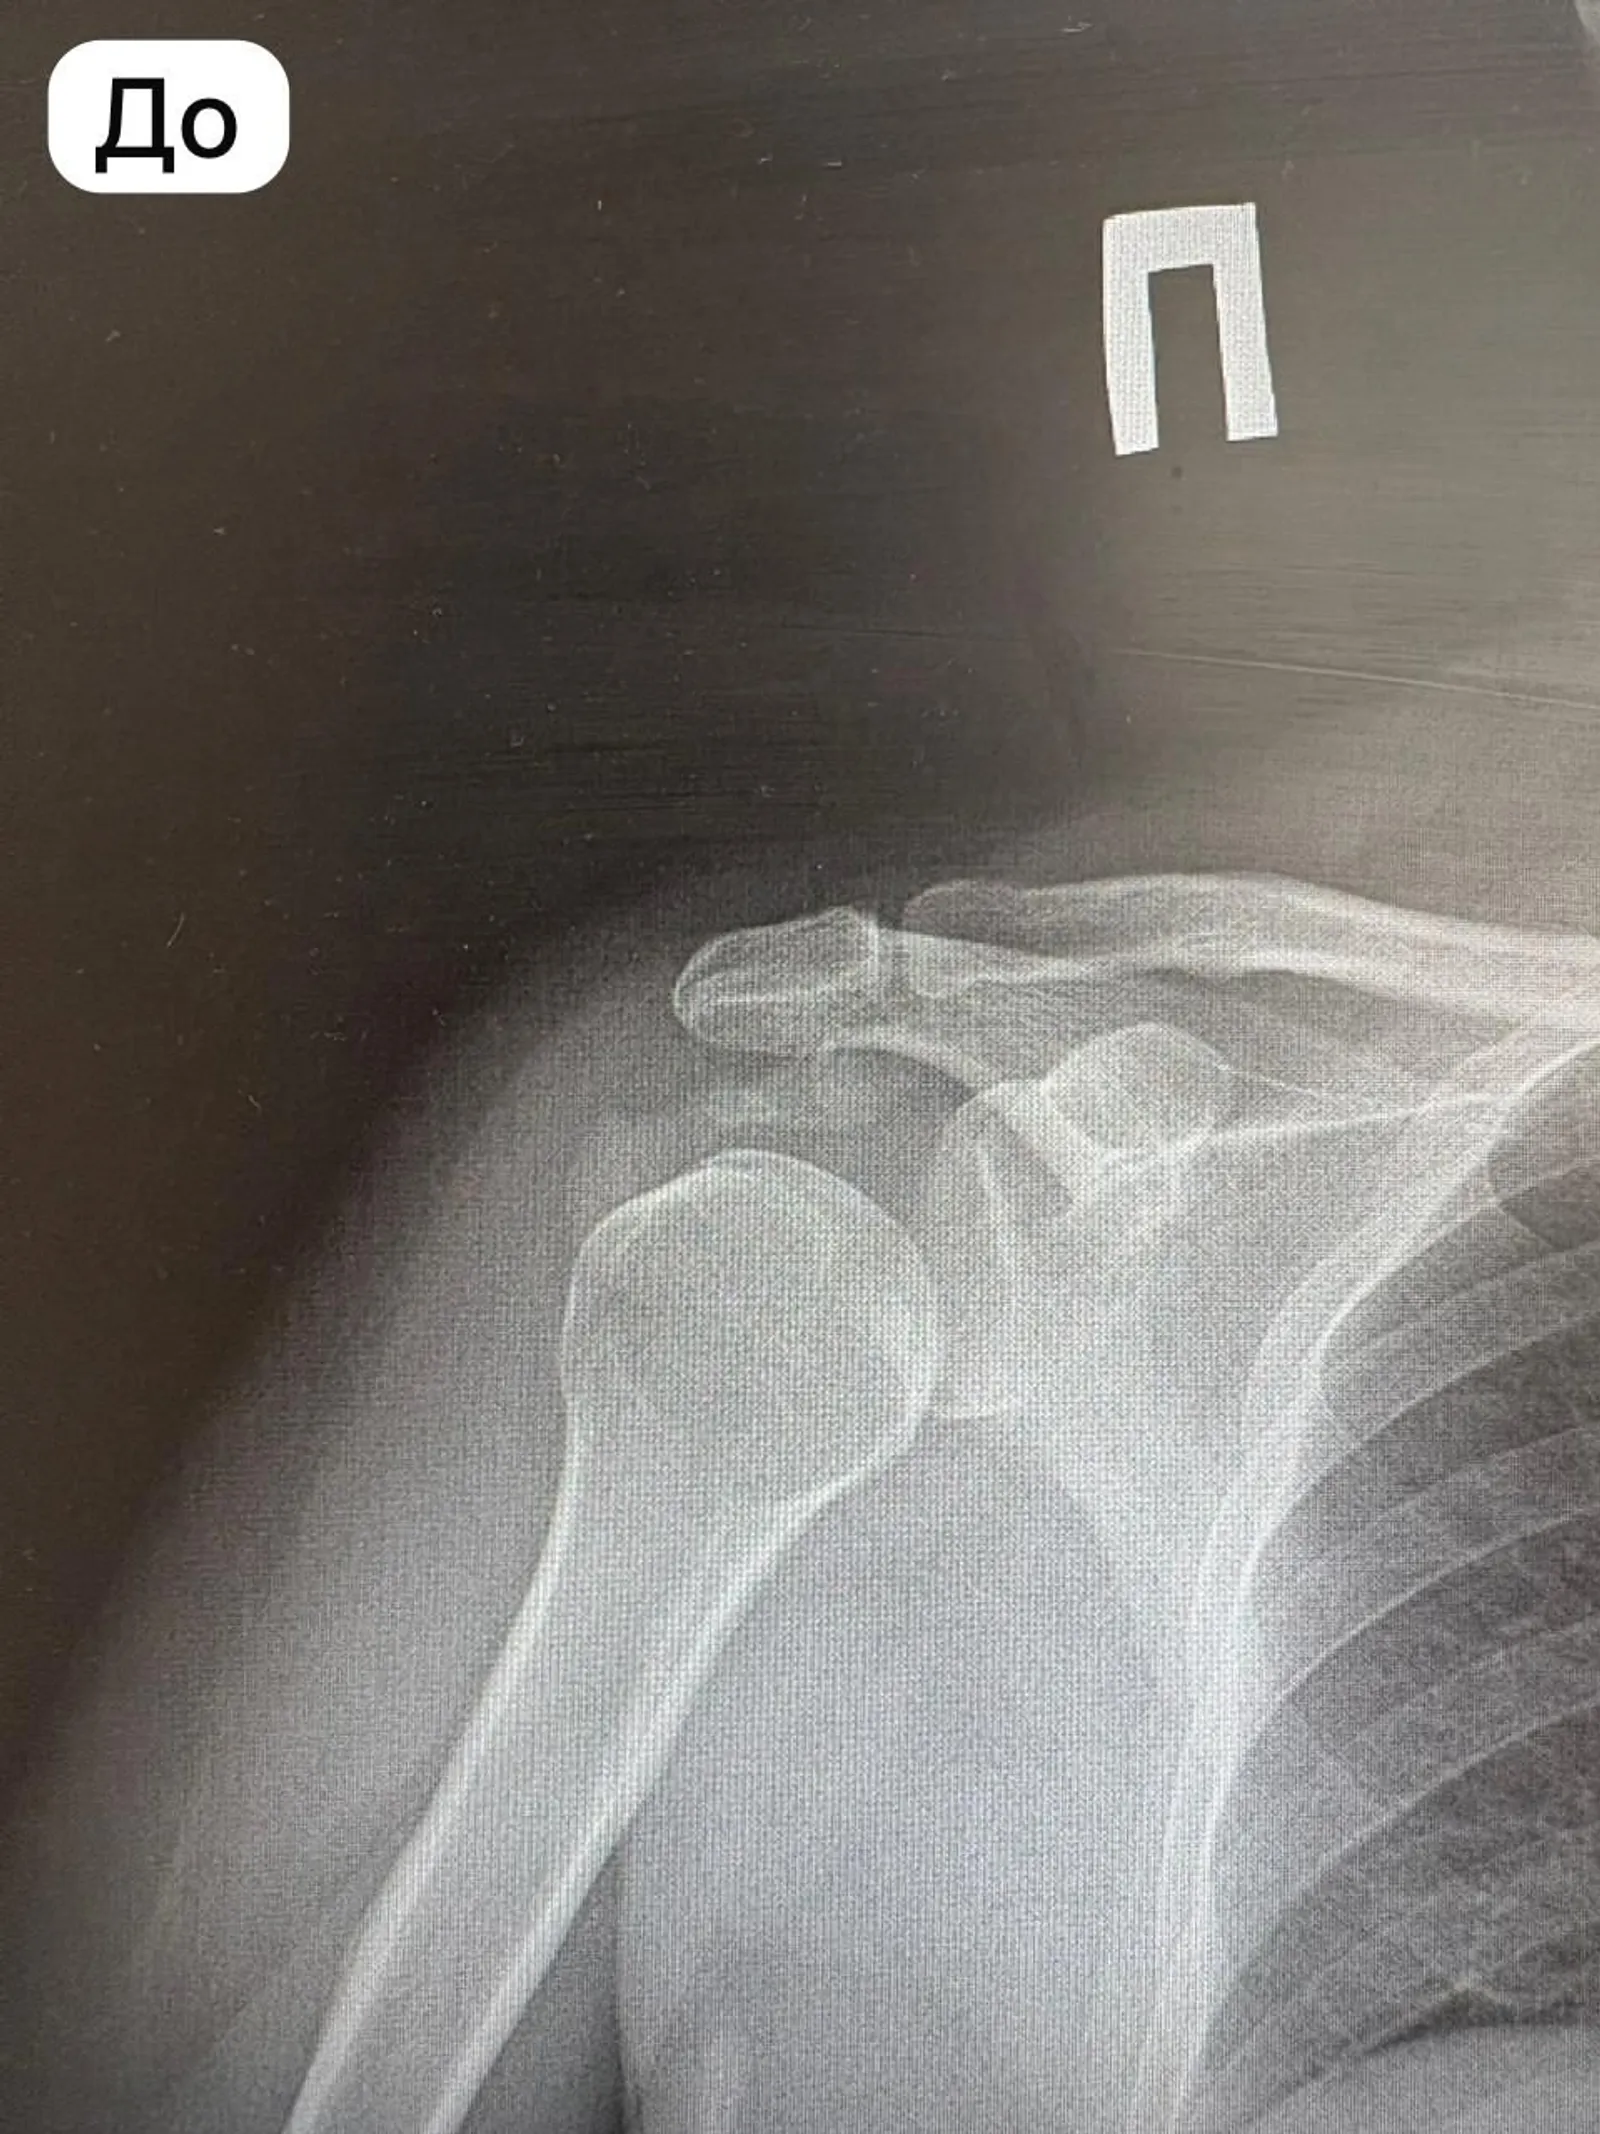

В городской клинической больнице №1 Стерлитамака впервые врачи инновационным методом удалили пациенту отложения кальцината плечевого сустава. Процедура называется барбатаж, пояснил главврач Ильшат Яппаров.

Врачи отделения травматологии и ортопедии через небольшие игольчатые проколы, без единого надреза, удалили кальциевые отложения объемом 2 см³. Тем самым избавили мужчину от болей и увеличили подвижность суставов.